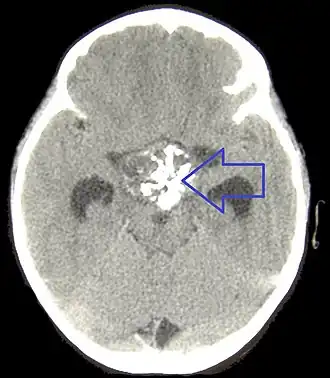

CT scan of the brain showing a craniopharyngioma (white structure in the center of the image). This tumor may cause hypopituitarism and requires surgical removal.

If one of these tests shows a deficiency of hormones produced by the pituitary, magnetic resonance imaging (MRI) scan of the pituitary is the first step in identifying an underlying cause. MRI may show various tumors and may assist in delineating other causes. Tumors smaller than 1 cm are referred to as microadenomas, and larger lesions are called macroadenomas.[1] Computed tomography with radiocontrast may be used if MRI is not available.[8] Formal visual field testing by perimetry is recommended, as this would show evidence of optic nerve compression by a tumor.[8]